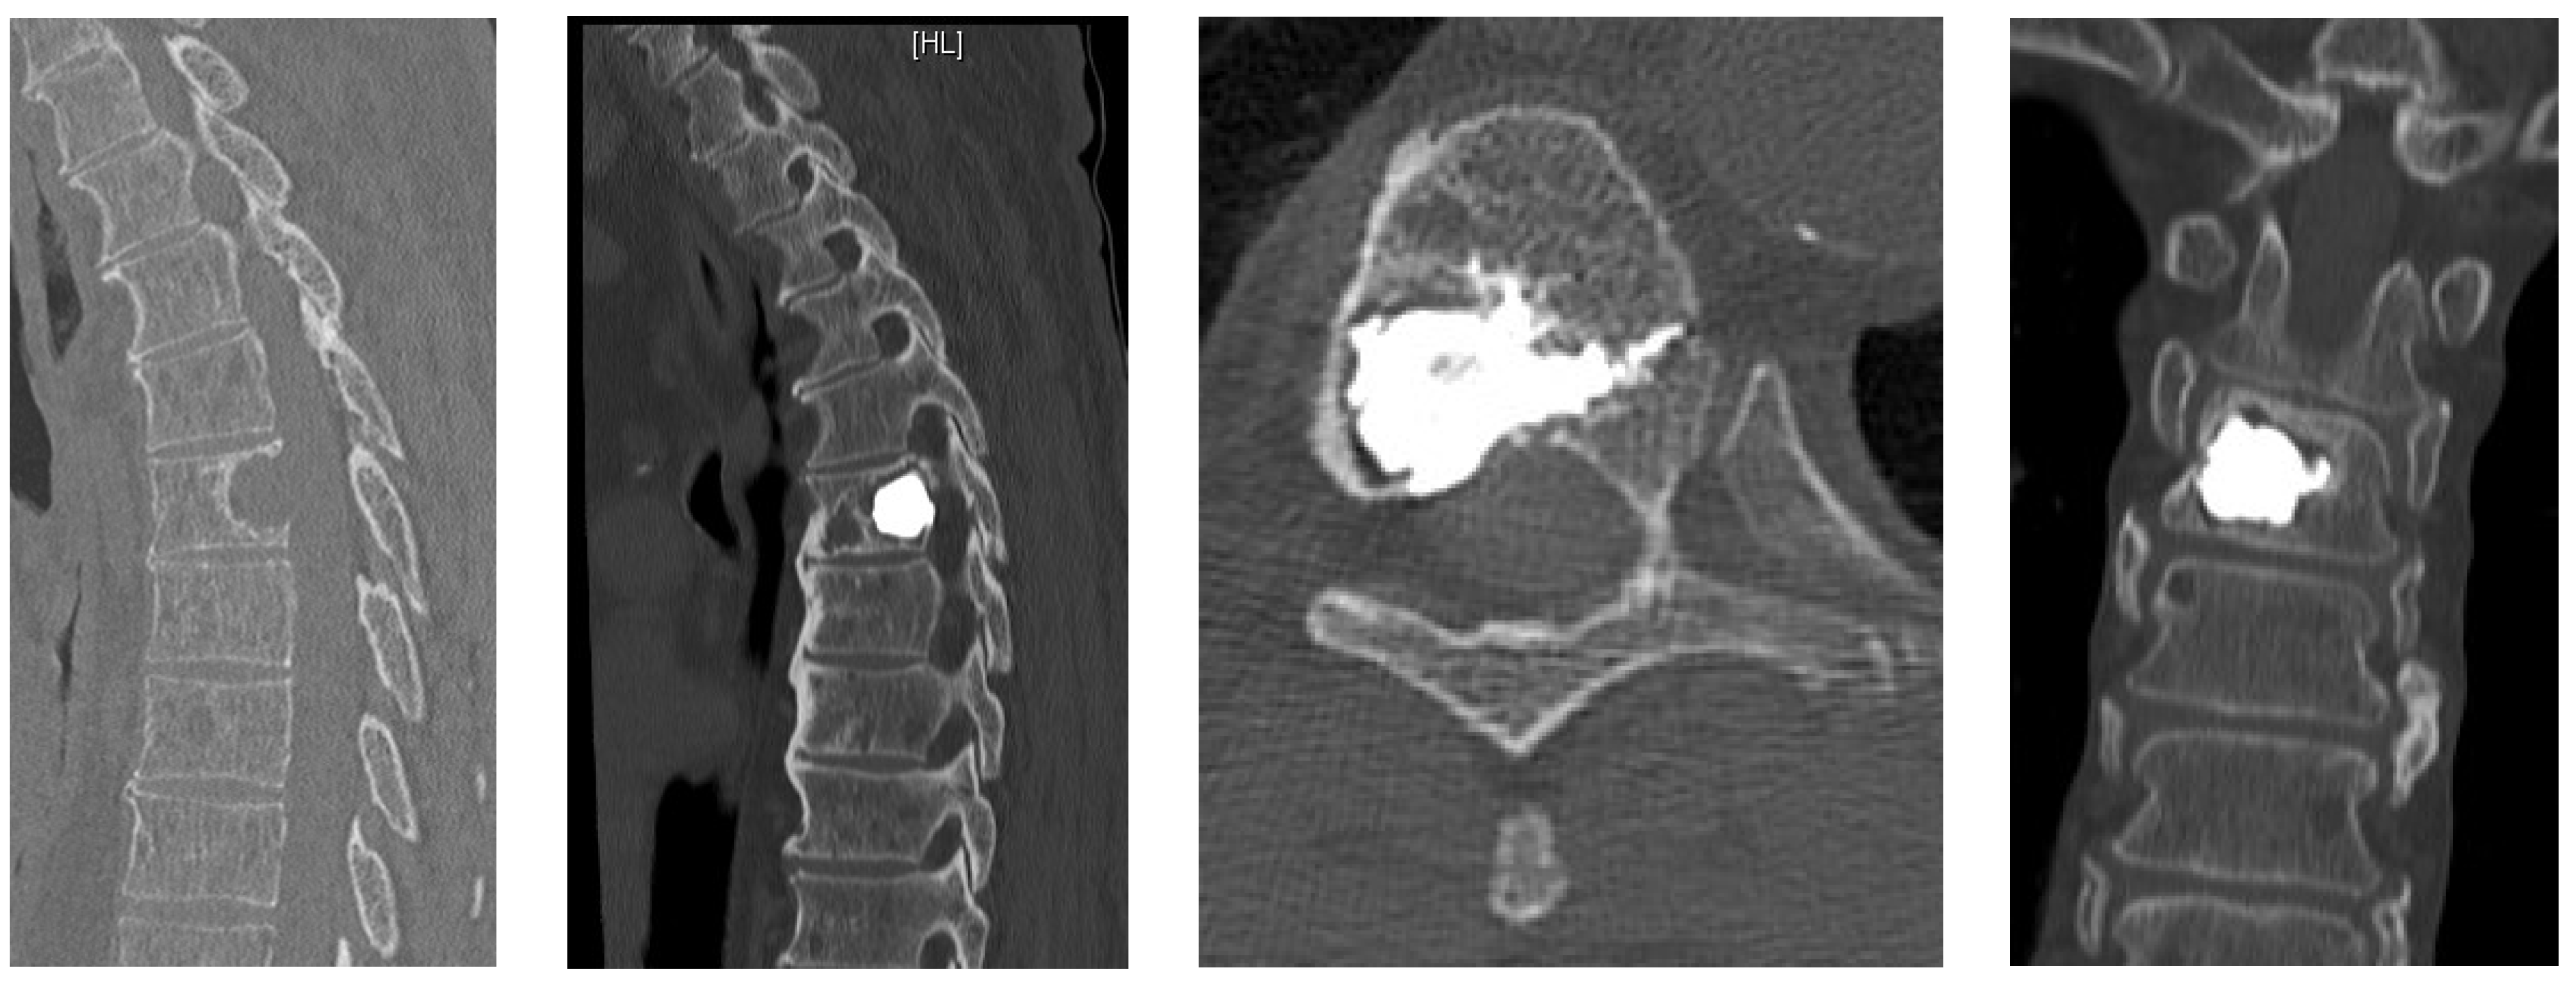

- Posterior percutaneous kyphoplasty for cervical spine metastases (Figure 2); case of C2-C3 kyphoplasty.

- Metastatic lesions of C1 are extremely rare, and their treatment by percutaneous cement augmentation is considered to be a technically challenging procedure due to complex anatomy. We also performed percutaneous kyphoplasty in a painful osteolytic lesion located on the left lateral mass of C1 through a posterolateral approach using a 3D CT scan intra-operative navigation system and fluoroscopy (Figure 3) [22].